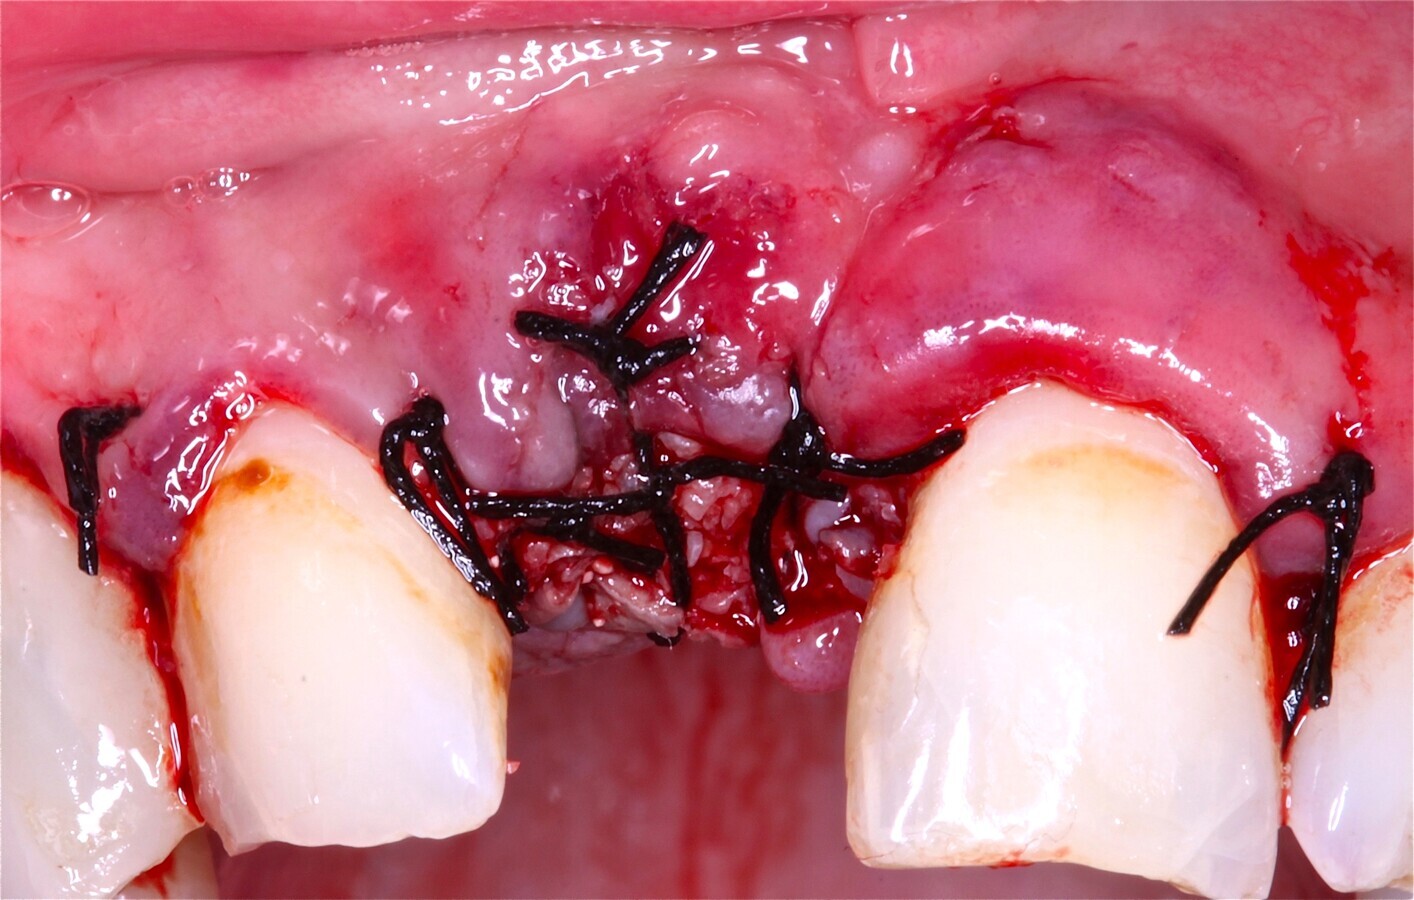

Fig. 12 Figura 12

1. Reposición del colgajo mucoperióstico, en el caso de la liberación del perióstico para garantizar un colgajo sin tensión, cierre primario del lecho10.

2. Sutura del colgajo con puntos simples y colchoneros horizontales con sutura 4/011,12.